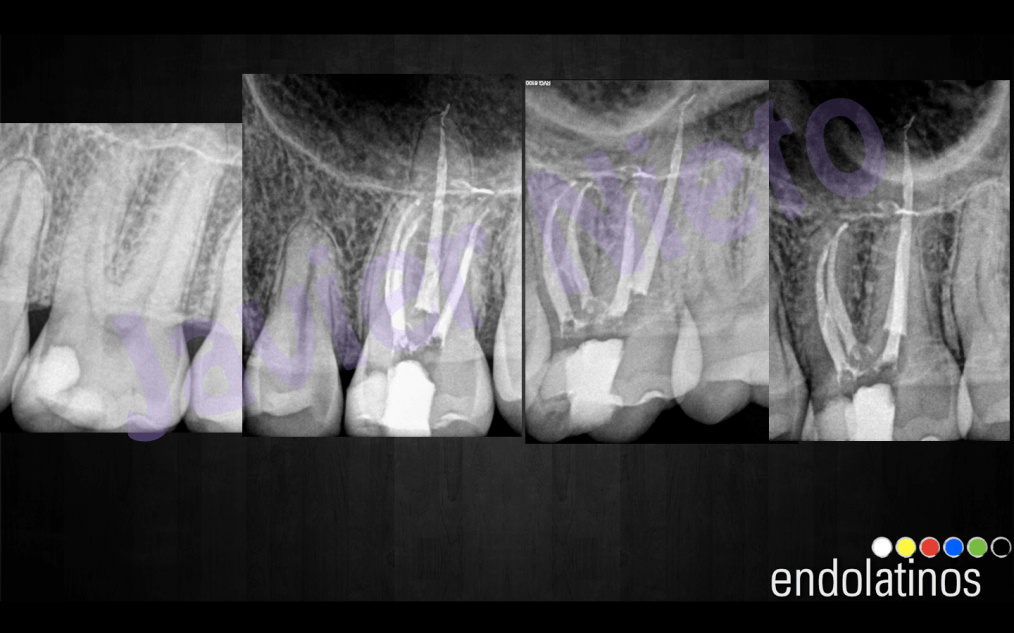

Caso 1:

Se trata de un paciente joven, 25 años de edad, diagnosticado con una pulpitis irreversible, se instrumentaron los conductos con el sistema de limas rotatorias de Ni-Ti , Mtwo, hasta un 25-6%. Procuramos hacer hincapié en la fase de irrigación, ya que conformamos el conducto bastante rápido, por tratarse de sistemas de conductos amplios, y sospechabamos de itsmos mesiales en su anatomía, con lo que debíamos eliminar el tejido pulpar. Usamos hipoclorito al 5% activandolo después de haber irrigado con EDTA para eliminar la capa de barrillo dentinario. Se activó con las Irrisafe, y después dejamos actuar al hipoclorito durante dos fases de 3 minutos. Se obturó con condensación vertical con la técnica de Ola continua de Buchanan algo modificada, creando más masa de gutapercha en la parte del tercio medio y apical. Un backfilling con una técnica de gutapercha inyectada con la pistola Obtura III.